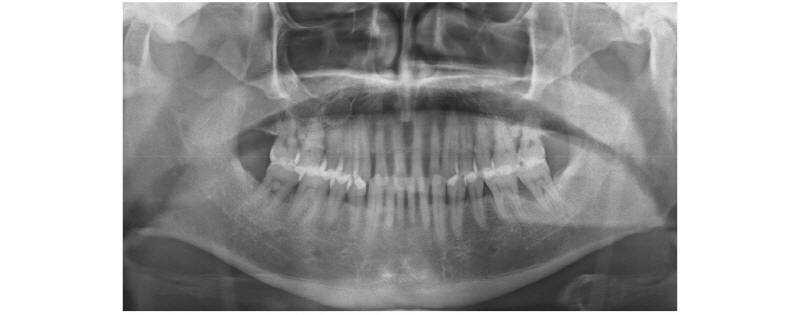

55세 남환이 금일 점심식사 하다가 하악 좌측 어금니가 깨졌다고 하여 내원하였다. 구강 내 소견은 하악 좌측 제1대구치의 설측 교두 두 개를 포함하여 치은 하방의 치근분지부까지 파절이 진행되었고, 치주질환으로 수직적 골결손이 많이 진행된 제2대구치를 포함하여 해당 치아 발치 후 두 개의 임플란트를 식립하기로 하였다(Fig. 1). 내부연결형 임플란트(TSIII, Osstem, Busan, Korea) 두 개를 식립하였고, 골유착이 충분히 이루어진 이후 보철과로 재내원하였다. 비디오 촬영 방식의 구강스캐너(Trios, 3shape, Copenhagen Denmark)를 이용하여 디지털 인상 채득을 시행하였다. 식립된 임플란트에 맞는 디지털 인상용 코핑(Scanbody, DIO Implant, Busan, Korea)을 임플란트 식립체 상단에 연결하고 파우더를 뿌리지 않는 방식의 구강스캐너로 디지털 영상을 획득하였다. 치유지대주를 푼 다음 임플란트의 치은 연하 형태와 인접 치아의 측면을 포함하여 하악 좌측 편악을 스캔하고, 스캔바디를 연결한 후 그 주변을 추가 스캔하였다. 이후 대합 치열을 스캔하고, 반대편 어금니로 최대감합위까지 교합된 상태를 유지하며, 측방 바이트 채득 기능을 이용하여 교합을 인기하였다. 기공소로 데이터를 전송하기 전에 스캔 데이터를 확인하여 전치부의 교합 양상이 환자의 실제 교합과 동일한지 확인하였다.

57세 여환이 오랫동안 쓰던 3본 고정성 가공의치가 불편하여 내원하였다. 상악 우측 제2대구치아 접착제 소실로 2차우식이 상당히 진행되어 있었으며, 발치 후 제2소구치는 고정성 가공의치를 자른 후 금관으로 그대로 사용하고, 제1, 2대구치 부위에 임플란트 치료를 하기로 하였다(Fig. 8). 내부 연결형 임플란트(TSIII, Osstem)를 식립하였고, 스캔바디를 이용하여 디지털 인상채득 후 티타늄 맞춤형 지대주, SCRP 전부지르코니아관을 CAD/CAM 제작하였으며, 시착 모형을 3D 프린트 적층 제작하였다. 환자는 재건된 수복물에 만족하였다(Fig. 9).

41세 남환이 어금니가 찬 물, 미지근한 물에 시리다는 주소로 내원하였다. BO inlay 근심과 협측에 잔금이 가 있었고, 치아 파절로 진단을 내리고 발치 후 임플란트(TSIII, Osstem) 식립을 하였다(Fig. 10). 디지털 인상 채득 후 맞춤형 지대주와 전부지르코니아관을 제작하였고, 시착 모형을 3D 프린터로 제작하였다(Fig. 11). 환자는 교합 기능과 심미적으로 모두 만족하였다(Fig. 12).